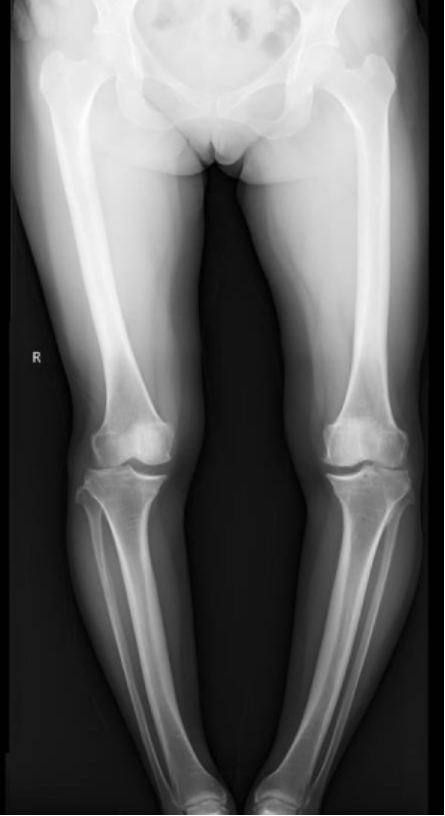

李彬在詳細(xì)了解了董阿姨的病史、進(jìn)行了全面的體格檢查和相關(guān)的輔助檢查后,組織科室進(jìn)行了深入的討論。最終的“答案”是——雙膝骨性關(guān)節(jié)炎、雙膝關(guān)節(jié)畸形、骨質(zhì)疏松以及雙膝半月板損傷。

面對(duì)這樣復(fù)雜且嚴(yán)重的病情,李彬并沒(méi)有退縮。他深知,對(duì)于董阿姨來(lái)說(shuō),這不僅僅是一次手術(shù),更是一次重生的機(jī)會(huì)。因此,他精心制定了手術(shù)方案:對(duì)雙下肢脛骨近端、遠(yuǎn)端以及雙側(cè)腓骨遠(yuǎn)端進(jìn)行截骨矯形,并進(jìn)行植骨內(nèi)固定。這樣的手術(shù)方案,無(wú)疑是對(duì)醫(yī)生技術(shù)的一次高難度挑戰(zhàn)!

手術(shù)前 手術(shù)后

手術(shù)很成功!經(jīng)過(guò)精心的治療和護(hù)理,董阿姨在9月順利出院。當(dāng)她再次站在鏡前時(shí),她驚喜地發(fā)現(xiàn)自己仿佛長(zhǎng)高了一截,那份曾經(jīng)讓她備受折磨的疼痛與不適也逐漸消失了。